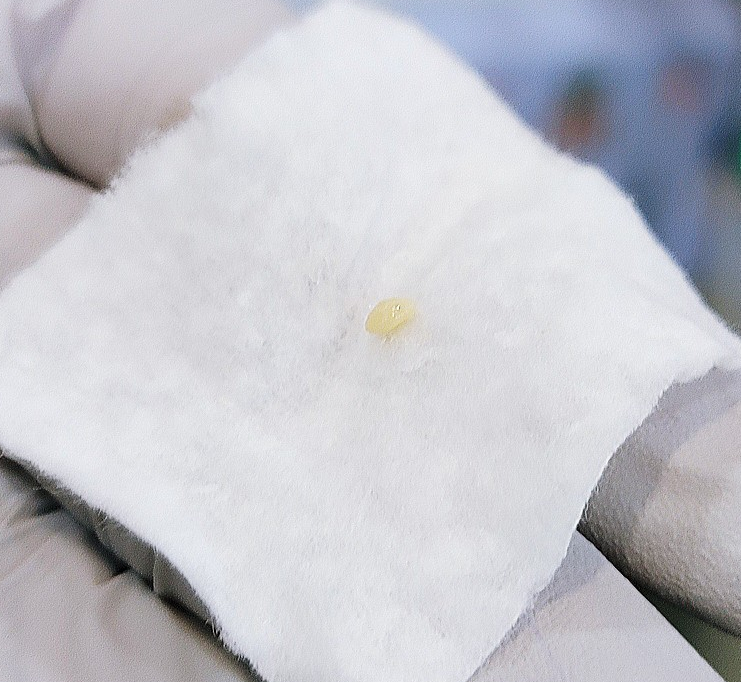

WoW…… 역시 예상대로 편도결석이 맞아서 의사고객님께서 흡입기(?)로 제거해주셨다.구역질이 나서 죽을뻔했다………눈물 또 흘립니다………지금보니 가끔 입안에서 저런 돌멩이?가 나오니까..내가 양치질을 안해서, 지금까지 먹은것중 하나인줄 알았는데..ㅋㅋㅋㅋㅋㅋㅋㅋㅋㅋㅋㅋㅋㅋㅋㅋㅋㅋㅋㅋㅋㅋㅋㅋㅋㅋㅋㅋㅋㅋㅋㅋ지금보니 그동안 편도결석이 저절로 떨어진것 같다.탱글탱글 이번에는 목의 붓기가 동시에 일어나 민감하게 받아들인 결과로 빨리 발견한 것 같습니다.